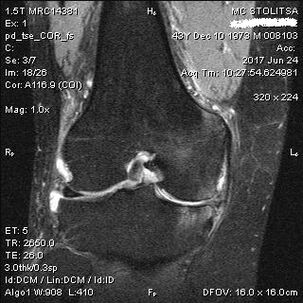

El diagnóstico de artritis de rodilla se realiza en el consultorio de un reumatólogo o un cirujano ortopédico. El médico examina y palpa las articulaciones afectadas, escucha quejas y hace otras preguntas. Realice varias pruebas, por ejemplo, pidiéndole al paciente que doble las piernas o dé algunos pasos. Luego lo remitirá para realizar más estudios si es necesario aclarar el estadio de la enfermedad o la naturaleza de los cambios patológicos. Por ejemplo, para tomografía computarizada o radiografía.